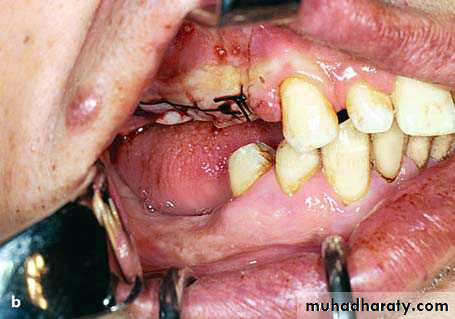

Localized Mandibular Buccal ExostosisThis case presents rarely, and, depending on its size, creates esthetic and functional problems in edentulous as well as dentulous patients. Its presence especially in edentulous patients obstructs the placement of complete dentures, in which case its removal is deemed necessary.

Mental nerve

Small trough created at the base of the exostosis with a fissure burRemoval of bone along the line of cleavage completed. Removal is performed using a chisel

Removal of the excised portion of the exostosis with a hemostat